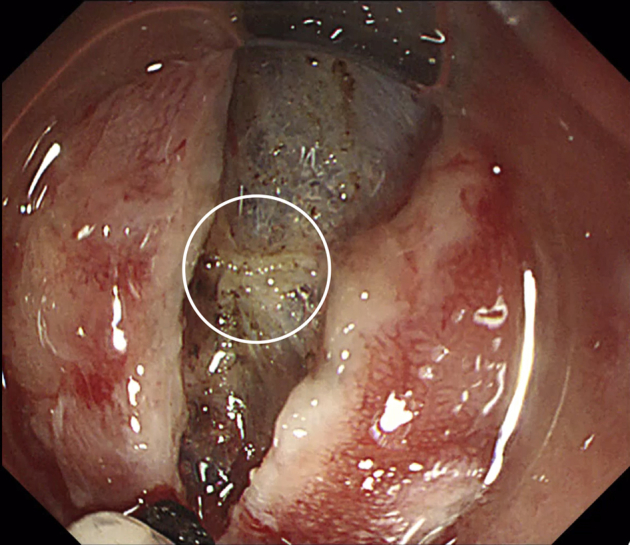

Figure 5.

Precise recognition of the bleeding vessel immediately after suctioning.

Figure 6.

Successful hemostasis of the bleeding vessel with the tip of the Endosaber.